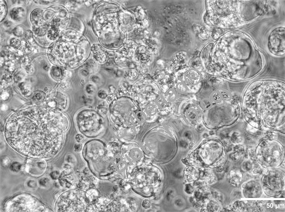

组成:500 μm GelMA微凝胶(EFL-GM-30),包裹骨髓间充质干细胞(BMSCs)。

制备:采用电喷雾技术生成尺寸均一的微凝胶,内部形成仿细胞外基质(ECM)的三维微环境。

功能:提供类Bingham流体特性——静止时如固体抵抗形变,挤出时如液体流动。